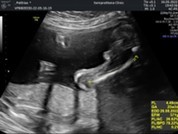

22 week หมอบอกน้องขายาวมาก😆

4 เดือนครึ่งค่ะ